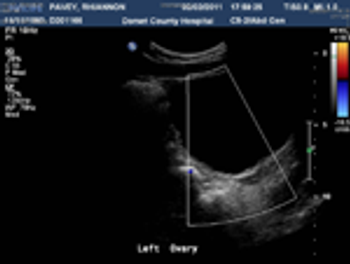

A 29-year-old gravida 10, para 3 (1 term gestation, 1 preterm gestation of twins, 1 stillbirth at 5 months, 2 spontaneous abortions, and 4 elective abortions) presented to the clinic at about 5 weeks’ gestation with abdominal pain and vaginal bleeding. She described the pain as sporadic, mostly on the left side, exacerbated by movement, and resolving with rest, and the bleeding as initially intermittent but then heavier “like a period.”